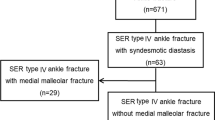

Gu et al. [15] included patients with MCS ≥ 5 mm on preoperative stress radiographs, with magnetic resonance imaging (MRI) confirming both superficial and deep deltoid. Woo et al. [16] repaired the DL in patients with MCS > 4 mm, MCS 1 mm greater than the superior tibiotalar clear space, or any lateral tibial shift on intraoperative stress views after fixation of the lateral malleolus and disrupted syndesmosis if observed. Zhao et al. [17] included adult patients with MCS ≥ 6 mm on preoperative anteroposterior ankle radiographs.

Ankle fracture dislocations with isolated lateral malleolus fractures were included in the study of Gu et al. [15]; after fixation of the lateral malleolus, a medial incision was made with repair of the DL using anchor sutures. Woo et al. [16] included patients with SER or PER ankle injuries, with an isolated lateral malleolus fracture, after repairing the lateral malleolus plus/minus syndesmotic fixation, as indicated by the cotton test [18]; a medial incision was made and the DL was fixed with 1 or 2 anchor sutures in the medial malleolus, 5 mm lateral to the medial talus. Zhao et al. [17] repaired the DL in SER, PER, and pronation-abduction injuries, after fixation of the lateral malleolus fractures, indicated posterior malleolus fractures and disrupted syndesmosis, as observed by intraoperative images. The DL was repaired through a medial incision, direct suturing to the talus or medial malleolus augmented with anchor suture, and suturing of the superficial deltoid with an absorbable material.